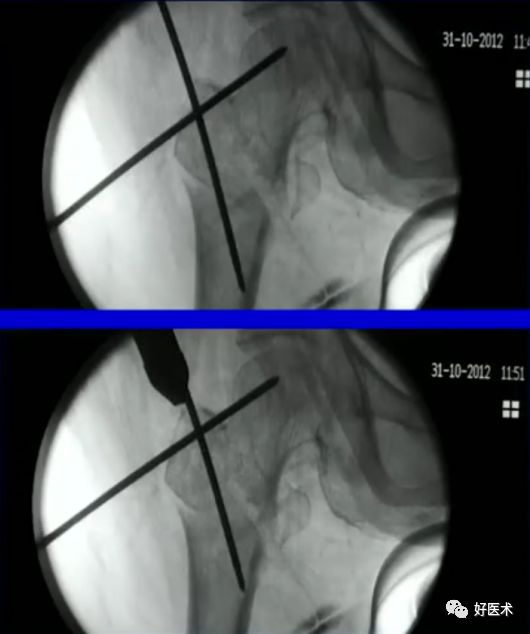

6.正确的股骨颈正侧位

侧卧位如何透股骨颈的侧位:

-

标准侧位

球管20-30°

侧卧位行转子间骨折固定